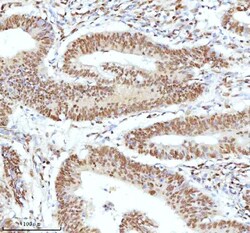

Reconstitute with 0.2 mL of distilled water to yield a concentration of 500 μg/mL. Positive Control - WB: human LNCAP whole cell, human Hela whole cell, human 293T whole cell, human HepG2 whole cell, human Jurkat whole cell, human K562 whole cell, human A549 whole cell, human A431 whole cell. IHC: human bladder cancer tissue, human bladder cancer tissue, human colon adenocarcinoma tissue, human colon adenocarcinoma tissue, human glioblastoma tissue, human glioblastoma tissue, human liver cancer tissue, human liver cancer tissue, human lung adenocarcinoma tissue, human lung adenocarcinoma tissue, human pancreas ductal adenocarcinoma tissue, human pancreas ductal adenocarcinoma tissue, human testicular seminoma tissue, human testicular seminoma tissue. ICC/IF: U2OS cell. Flow: A431 cell. Store at -20°C for one year from date of receipt. After reconstitution, at 4°C for one month. It can also be aliquotted and stored frozen at -20°C for six months. Avoid repeated freeze-thaw cycles.